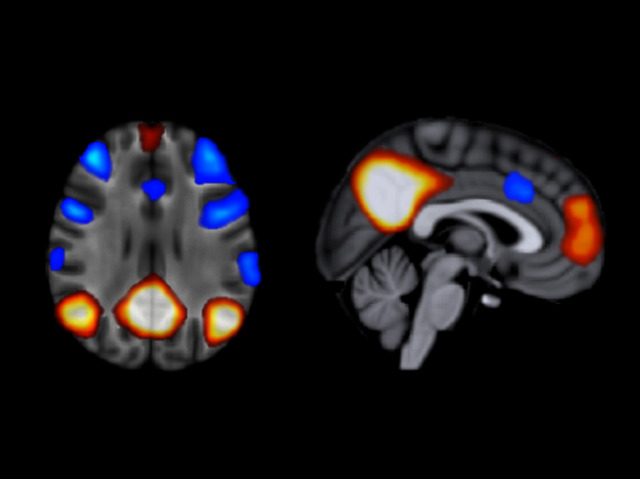

Schizophrenia Awareness Week Daydreams

When you daydream the pattern of activity in your brain, at least to a neuroscientist, is known as the default mode network. The recent discovery of this brain state came as something of a surprise since it occurs when you’re not actively thinking about or doing anything. Scientists can measure brain activity by looking at changes in the amount of oxygen carried by the blood to different parts of the brain. A technique called functional magnetic resonance imaging (fMRI) here highlights the ‘resting’ patterns of brain activity in 34 patients with schizophrenia. These data suggest that the default mode network may be altered in patients with schizophrenia, who still have symptoms despite taking medication. Now the challenge is to find out why.